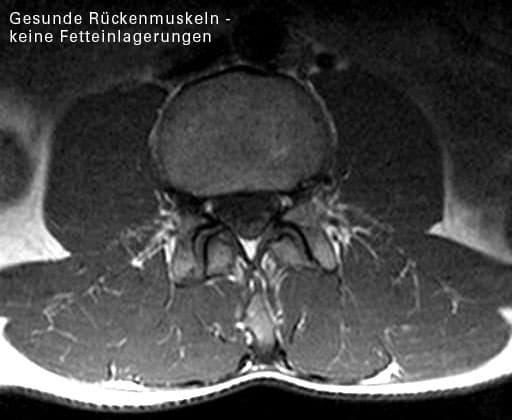

Hauptursache der chronischen LWS-Beschwerden ist eine Schwäche der Rückenmuskeln, genauer:

Eine Schwäche der Rückenstrecker, die rechts und links der LWS liegen und die im gesunden, guten Trainingszustand die Wülste neben der LWS bilden.

2. Bei chronischen Rückenbeschwerden zeigen die Rückenmuskeln

• einen Schwund von aktivem Muskelgewebe

• eine Umwandlung von Muskeln in Fettgewebe

• eine Umwandlung von Muskeln in Bindegewebe

• eine krankhafte Muskelaktivität

Die hat eine Ulmer Forschergruppe Ende der 90er Jahre nachgewiesen